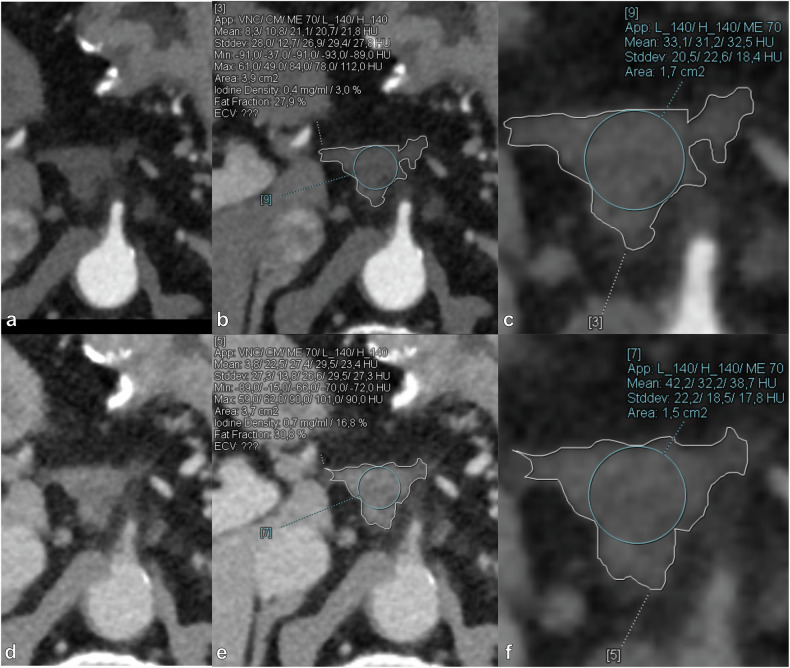

Methods: Seventy-three consecutive PCD-CT scans in 73 patients with postoperative soft-tissue lesions (PSLs) were included, 42 with POC and 31 with LTR. Regions of interest were drawn in each PSL, and spectral variables were calculated: iodine concentration (IC), normalized IC (NIC), fat fraction, attenuation at 40, 70, and 90 keV, and slope of the spectral curve between 40-90 keV. Multivariable binary logistic regression models were constructed. Diagnostic performance was assessed for LAP and PVP using receiver operating characteristic analysis.

Results: In LAP, all variables except fat fraction showed significant differences between LTR and POC (p ≤ 0.025). In PVP, all variables except NIC and fat fraction demonstrated significant differences between LTR and POC (p ≤ 0.005). Logistic regression analysis included NIC and 70 keV in the LAP-based model and IC and 90 keV in the PVP-based model. Both models achieved a higher area under the curve (AUC) than individual spectral variables in each phase. The LAP-based model achieved an AUC of 0.919 with 94% sensitivity, 84% specificity, and 87% accuracy, while the PVP-based model reached 0.820, 71%, 88%, and 81%, respectively.

Relevance statement: Measuring normalized iodine concentration and attenuation at 70 keV in late arterial phase, or iodine concentration and attenuation at 90 keV in portal venous phase, and incorporating these values into a logistic regression model can help differentiate between local tumor recurrence and postoperative changes after pancreatic ductal adenocarcinoma resection.

Key points: Distinguishing recurrence from postoperative changes on CT after pancreatic ductal adenocarcinoma resection is challenging. PCD-CT spectral variable values differed significantly between local tumor recurrence (LTR) and postoperative changes (POC). Logistic regression of spectral variables can help distinguish LTR from POC. The late arterial phase-based model reached an AUC of 0.919 with 94% sensitivity and 84% specificity.